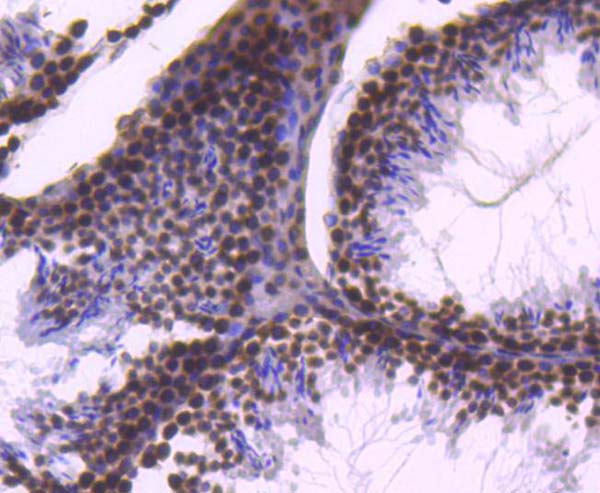

Ki67, Monoclonal Antibody (Cat# AAA19350)